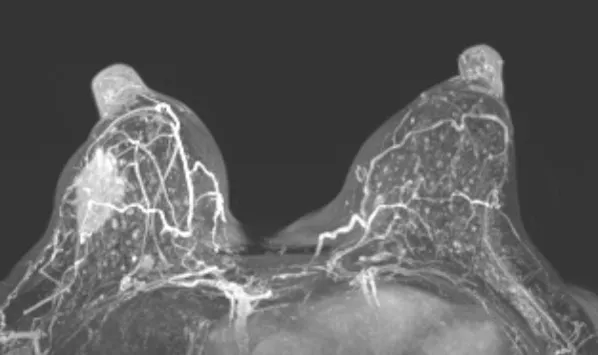

在靶区固定环节,中心采用自主研发的乳腺固定器(实用新型专利号:ZL202221125437.4)联合负压垫、热塑体膜的三重固定技术,从源头上解决靶区移位难题,为精准放疗筑牢基础。剂量方案上,摒弃日本单一剂量模式,根据肿瘤大小、距皮肤距离、病理类型等个体差异精准制定:肿瘤靶区给予72-80Gy(RBE)根治剂量,全乳及淋巴引流区给予40Gy(RBE)预防剂量,阳性淋巴结按大小调整为48-60Gy(RBE)。同时,通过多野照射技术优化剂量分布,最大限度降低皮肤受照剂量,显著减少放射性皮炎等并发症风险,真正实现“精准杀伤肿瘤、严格保护正常组织”的双重目标。